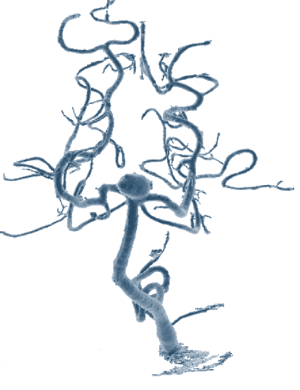

This page is dedicated to my cyber friends who support our group so willingly. It is dedicated to those patients with a congenital birth defect called an AVM (Arteriovenous Malformation) as well as all of the aneurysm patients throughout the world. Amazingly, there are only approximately 3 out of 10,000 of the population born with an AVM (.03%). I have included hyperlinks on information available on the web including an Aneurysm and AVM Support Page, information on AVM's, Aneurysms, Strokes, Brain Surgery and more.

What is an AVM?

This describes an Arteriovenous Malformation.

AVM Treatments by John Hopkins University

The decisions related to treatment for the brain AVM depend upon the complete understanding of the competing risks vs. benefits. The important considerations for treatment of the AVM include the size and location within the brain.